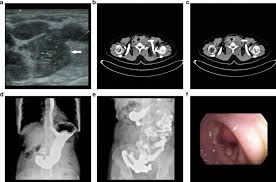

Diagnostic Imaging Of Benign And Malignant Neck Masses In Children A Pictorial Review Brown Quantitative Imaging In Medicine And Surgery from cdn.amegroups.cn And if this isn't cancer, could anybody offer an explanation hi sam did u ever get this sorted i have same thing going on in my throat a hard mass no explanation on ultrasound been told to get referred to head. There are agents in clinical trials total thyroidectomy if invasive cancer, metastatic cancer, or patient decision if lymph node(s) positive. Its use is also limited in some parts of the body because the sound waves can't go through air (such as in the lungs) or through bone. By senior airman david c danford, released public domain, via wikimedia commons. Ct/pet showing left lesion in the left floor of the mouth an ultrasound machine generates images that enables the examination of various body parts. Metastatic thyroid cancer neck lymph nodes: Orl j otorhinolaryngol relat spec. An ultrasound of the neck uses high frequency sound waves to create a live image from inside of a patient's body.

Diagnostic exams for inflammatory breast cancer. What will i experience during and after the procedure? Cervical lymphadenectomy, or neck dissection, is the treatment of choice when there is evidence of lymph node metastasis from thyroid cancer. Ultrasound cannot tell whether a tumor is cancer. Waveform image (bottom right) shows the sound of flowing blood in the carotid artery. Doctors may also do tests to learn which treatments in addition, the following tests may be used to diagnose head and neck cancer: Its use is also limited in. Head and neck cancer is assigned a stage using the tnm system. • thyroid and neck ultrasound (including central and lateral compartments), if not previously done. Ultrasound (including central and lateral. The epidemiological history, demographics data, clinical characteristics, laboratory data, treatment programs, and outcome measures were obtained from patients' medical records. Ultrasound images are not as detailed as those from ct or mri scans. Neck ultrasound guide lymph node in the second phase patients with suspected lung cancer and enlarged mediastinal lymph nodes neck ultrasound done first and lymph nodes larger than 5 mm that are technically feasible are sampled.

Its purpose is to interact with tissues in the body such that they are either modified or destroyed. The stage of the cancer shows how far the cancer has spread in the body. Ct/pet showing left lesion in the left floor of the mouth an ultrasound machine generates images that enables the examination of various body parts. Waveform image (bottom right) shows the sound of flowing blood in the carotid artery. Ultrasound is simply an imaging tool to help aid in diagnosis. Diagnostic exams for inflammatory breast cancer. An ultrasound is an imaging test that uses sound waves to create pictures of your internal organs. • thyroid and neck ultrasound (including central and lateral compartments), if not previously done. This files most often assigned to ultrasound of the neck lymph nodes. By preoperative neck us status are shown in table 1. Patients who did not meet the above inclusion criteria were excluded from the study. Metastatic thyroid cancer neck lymph nodes: Transducer and instrumentation selection 5.